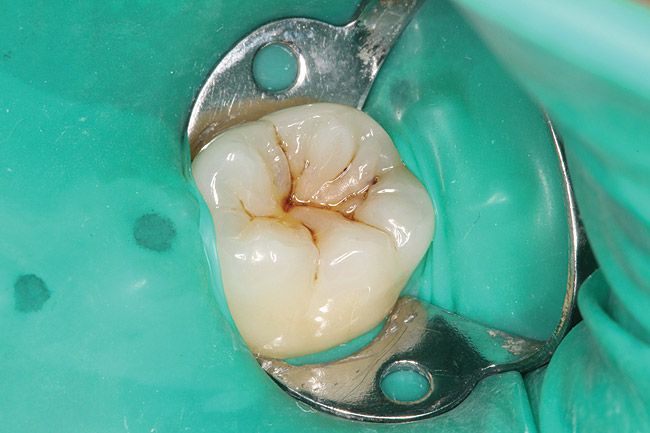

- Εκτεταμένη / βαθιά τερηδόνα, η οποία έχει διαπεράσει την οδοντίνη και έχει προσβάλλει τον πολφό (νεύρο του δοντιού).

- Τοποθετείται ένα ειδικό λάστιχο, που λέγεται απομονωτήρας